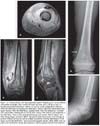

If CA-MRSA is suspected (Figure), the first-line options include administration of clindamycin and then the addition of vancomycin in critically ill patients.8 Vancomycin is the first-line agent for HA-MRSA infection. Clindamycin may be given as the first-line drug for CA-MRSA infection, particularly in patients who are allergic to or intolerant of b-lactam antibiotics. Although a number of the newer antibiotics (eg, daptomycin, dalbavancin, tigecycline, ceftobiprole, linezolid, and quinopristin/dalfopristin) have been shown to be effective against MRSA, these agents should be used only with the advice of an infection specialist.